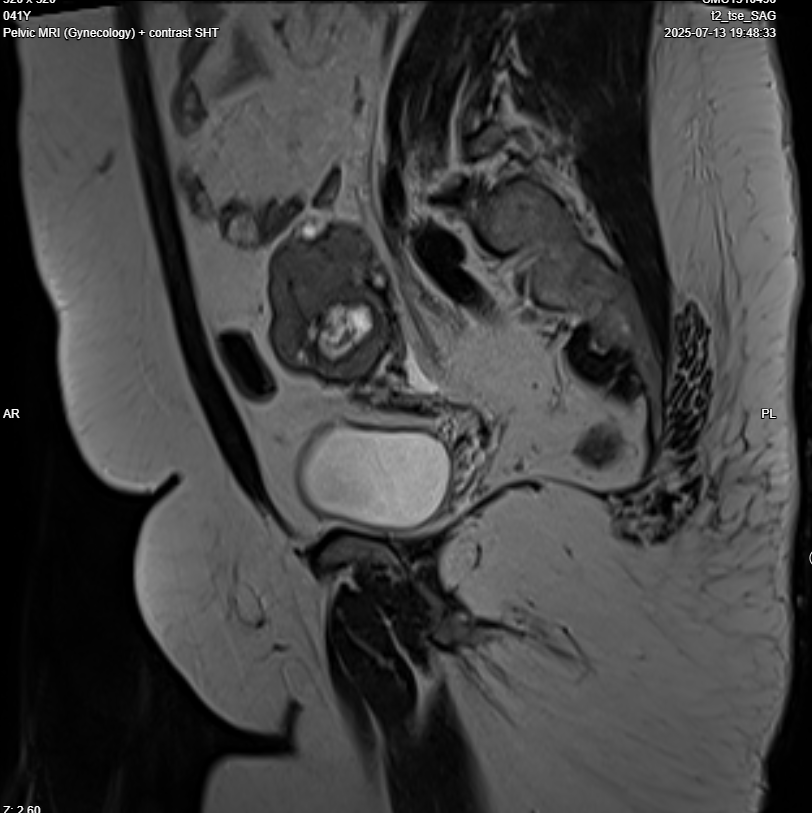

Pelvic MRI with IV contrast

· Evidence of left adnexal irregular lobulated shape solid mass replacing most of left ovarian parenchyma , T1 iso intense , T2 hypo intense , restricted in DWI, no fat , no calcification , after giving contrast showing diffuse progressive hyper enhancement , with high risk curve of enhancement , these radiological features highly suspicious for malignant ovarian tumor, O-RADS 5.